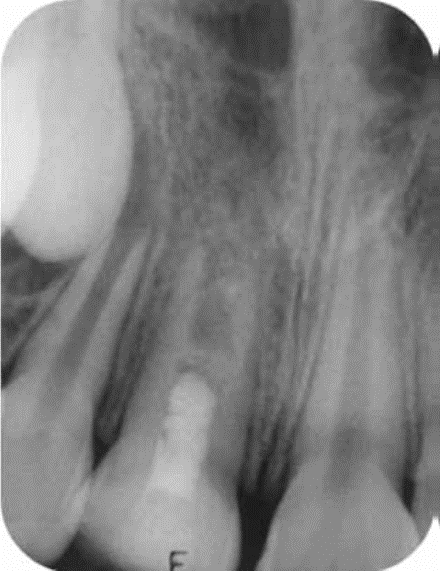

Varios reportes clínicos, han mostrado que dientes permanentes inmaduros diagnosticados con pulpas no vitales y periodontitis periapical o abscesos pueden presentar apexogènesis (apicogènesis). Estos reportes desafían el enfoque tradicional del manejo de este tipo de dientes mediante la apexificaciòn (apicoformación) donde no se espera que haya una continuación de desarrollo pulpar.

La apexificaciòn (apicoformación) induce el desarrollo posterior de un ápice para cerrar el foramen, pero NO promueve el engrosamiento de las paredes dentinarias del conducto radicular, permaneciendo débiles y proclives a la fractura.

Recientemente se ha descrito un procedimiento cuyo objetivo principal es la revascularización pulpar, llevando la aposición de tejido calcificado sobre las paredes del conducto pulpar y el ápice radicular mejorando el pronóstico de estos dientes a futuro. El factor clave para estos dientes infectados e inmaduros, es la desinfección del sistema de conductos radiculares. (4)

Partiendo de los casos de avulsión de dientes inmaduros, si son insertados en su alvéolo, en el menor tiempo posible, se puede comprobar la revascularización pulpar lo que favorece el desarrollo radicular con el engrosamiento de las paredes dentinarias. Si fuera posible crear un entorno semejante, como lo pretende la teoría de la Regeneración Endodòntica, pudiese ocurrir también la regeneración en los casos de dientes inmaduros infectados. Es posible, como lo han estado demostrando muchas investigaciones, que en estos dientes infectados y aún con lesión periapical o abscesos, restos de tejido pulpar y vaina Hertwig permanezcan vivos; sí se revierten estas condiciones pueden proliferar. (5)

Una vez ya seleccionado el caso correspondiente de acuerdo al diagnostico establecido y a las posibilidades de una posible revascularización, se elabora historia clínica y una serie de radiografías con diferentes angulaciones para poder llevar el caso su correspondiente control. A continuación, describiremos la técnica de Hoshino y col. y de Trope y col.